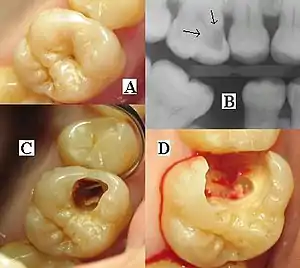

Montage of four pictures: three photographs and one radiograph of the same tooth.

(A) A small spot of decay visible on the surface of a tooth. (B) The radiograph reveals an extensive region of demineralization within the dentin (arrows). (C) A hole is discovered on the side of the tooth at the beginning of decay removal. (D) All decay removed; ready for a filling.

A person experiencing caries may not be aware of the disease.[12] The earliest sign of a new carious lesion is the appearance of a chalky white spot on the surface of the tooth, indicating an area of demineralization of enamel. This is referred to as a white spot lesion, an incipient carious lesion or a "micro-cavity".[13] As the lesion continues to demineralize, it can turn brown but will eventually turn into a cavitation ("cavity"). Before the cavity forms, the process is reversible, but once a cavity forms, the lost tooth structure cannot be regenerated. A lesion that appears dark brown and shiny suggests dental caries were once present but the demineralization process has stopped, leaving a stain. Active decay is lighter in color and dull in appearance.[14]